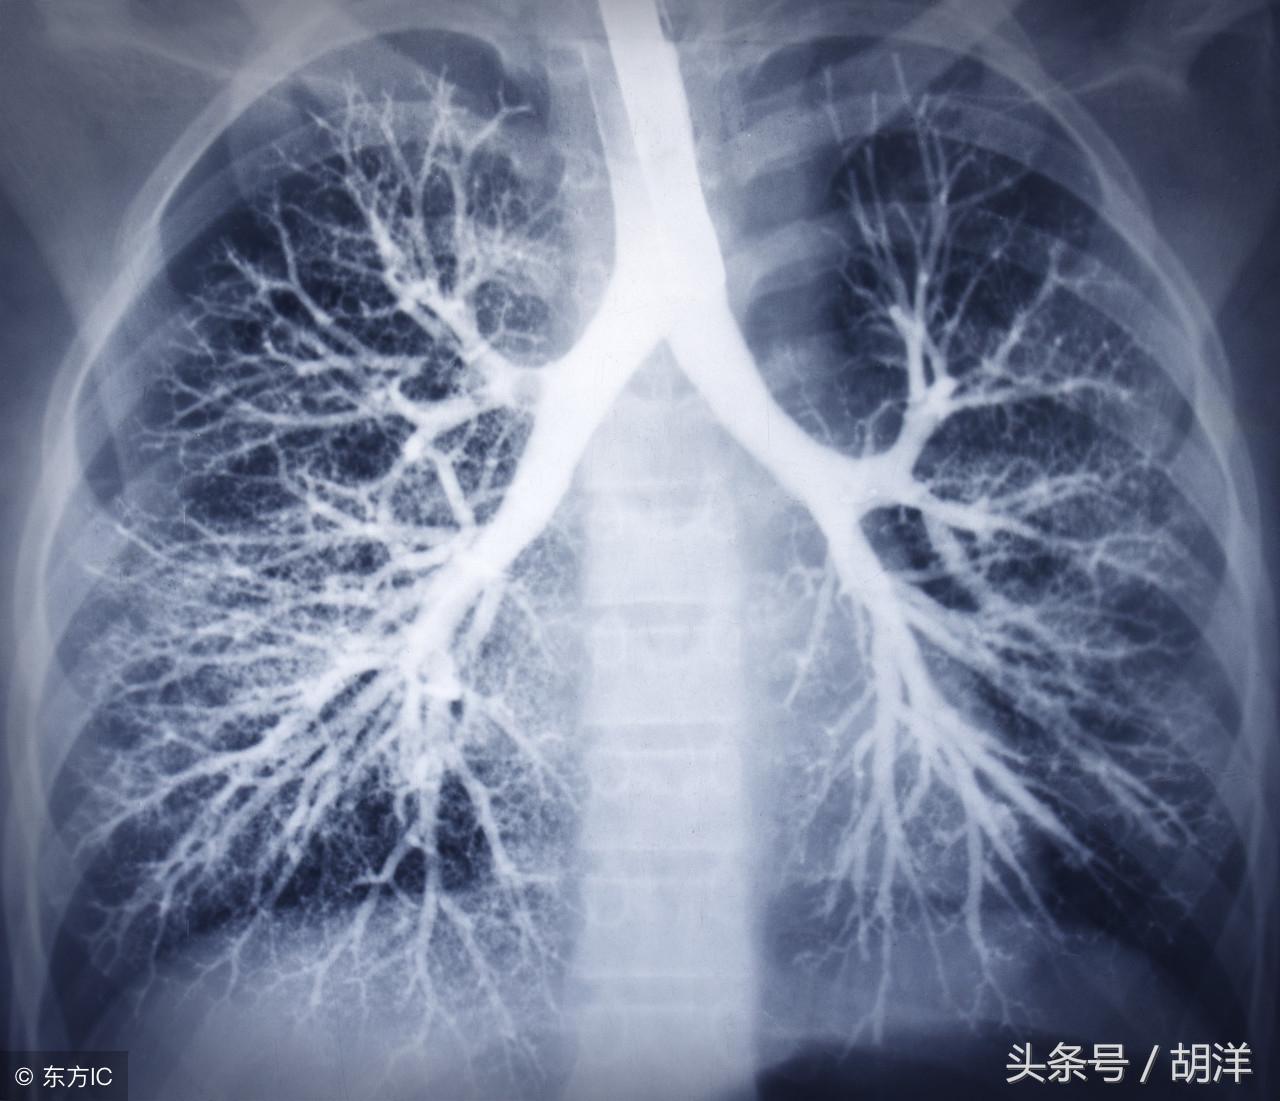

支气管扩张是一种支气管管壁结构破坏性疾病,正常情况下,支气管是一个带有弹性,拥有一定管径的能够维持正常呼吸通气的结构,当管壁结构受到破坏时,气管会受到被动的牵拉而扩张,管壁的血管由于弹性较小,容易被撕扯呈血管瘤改变,一旦胸腔内血流压力增大可能冲破血管瘤变薄的管壁而导致大咯血,少量渗血时则呈现为痰中带血。